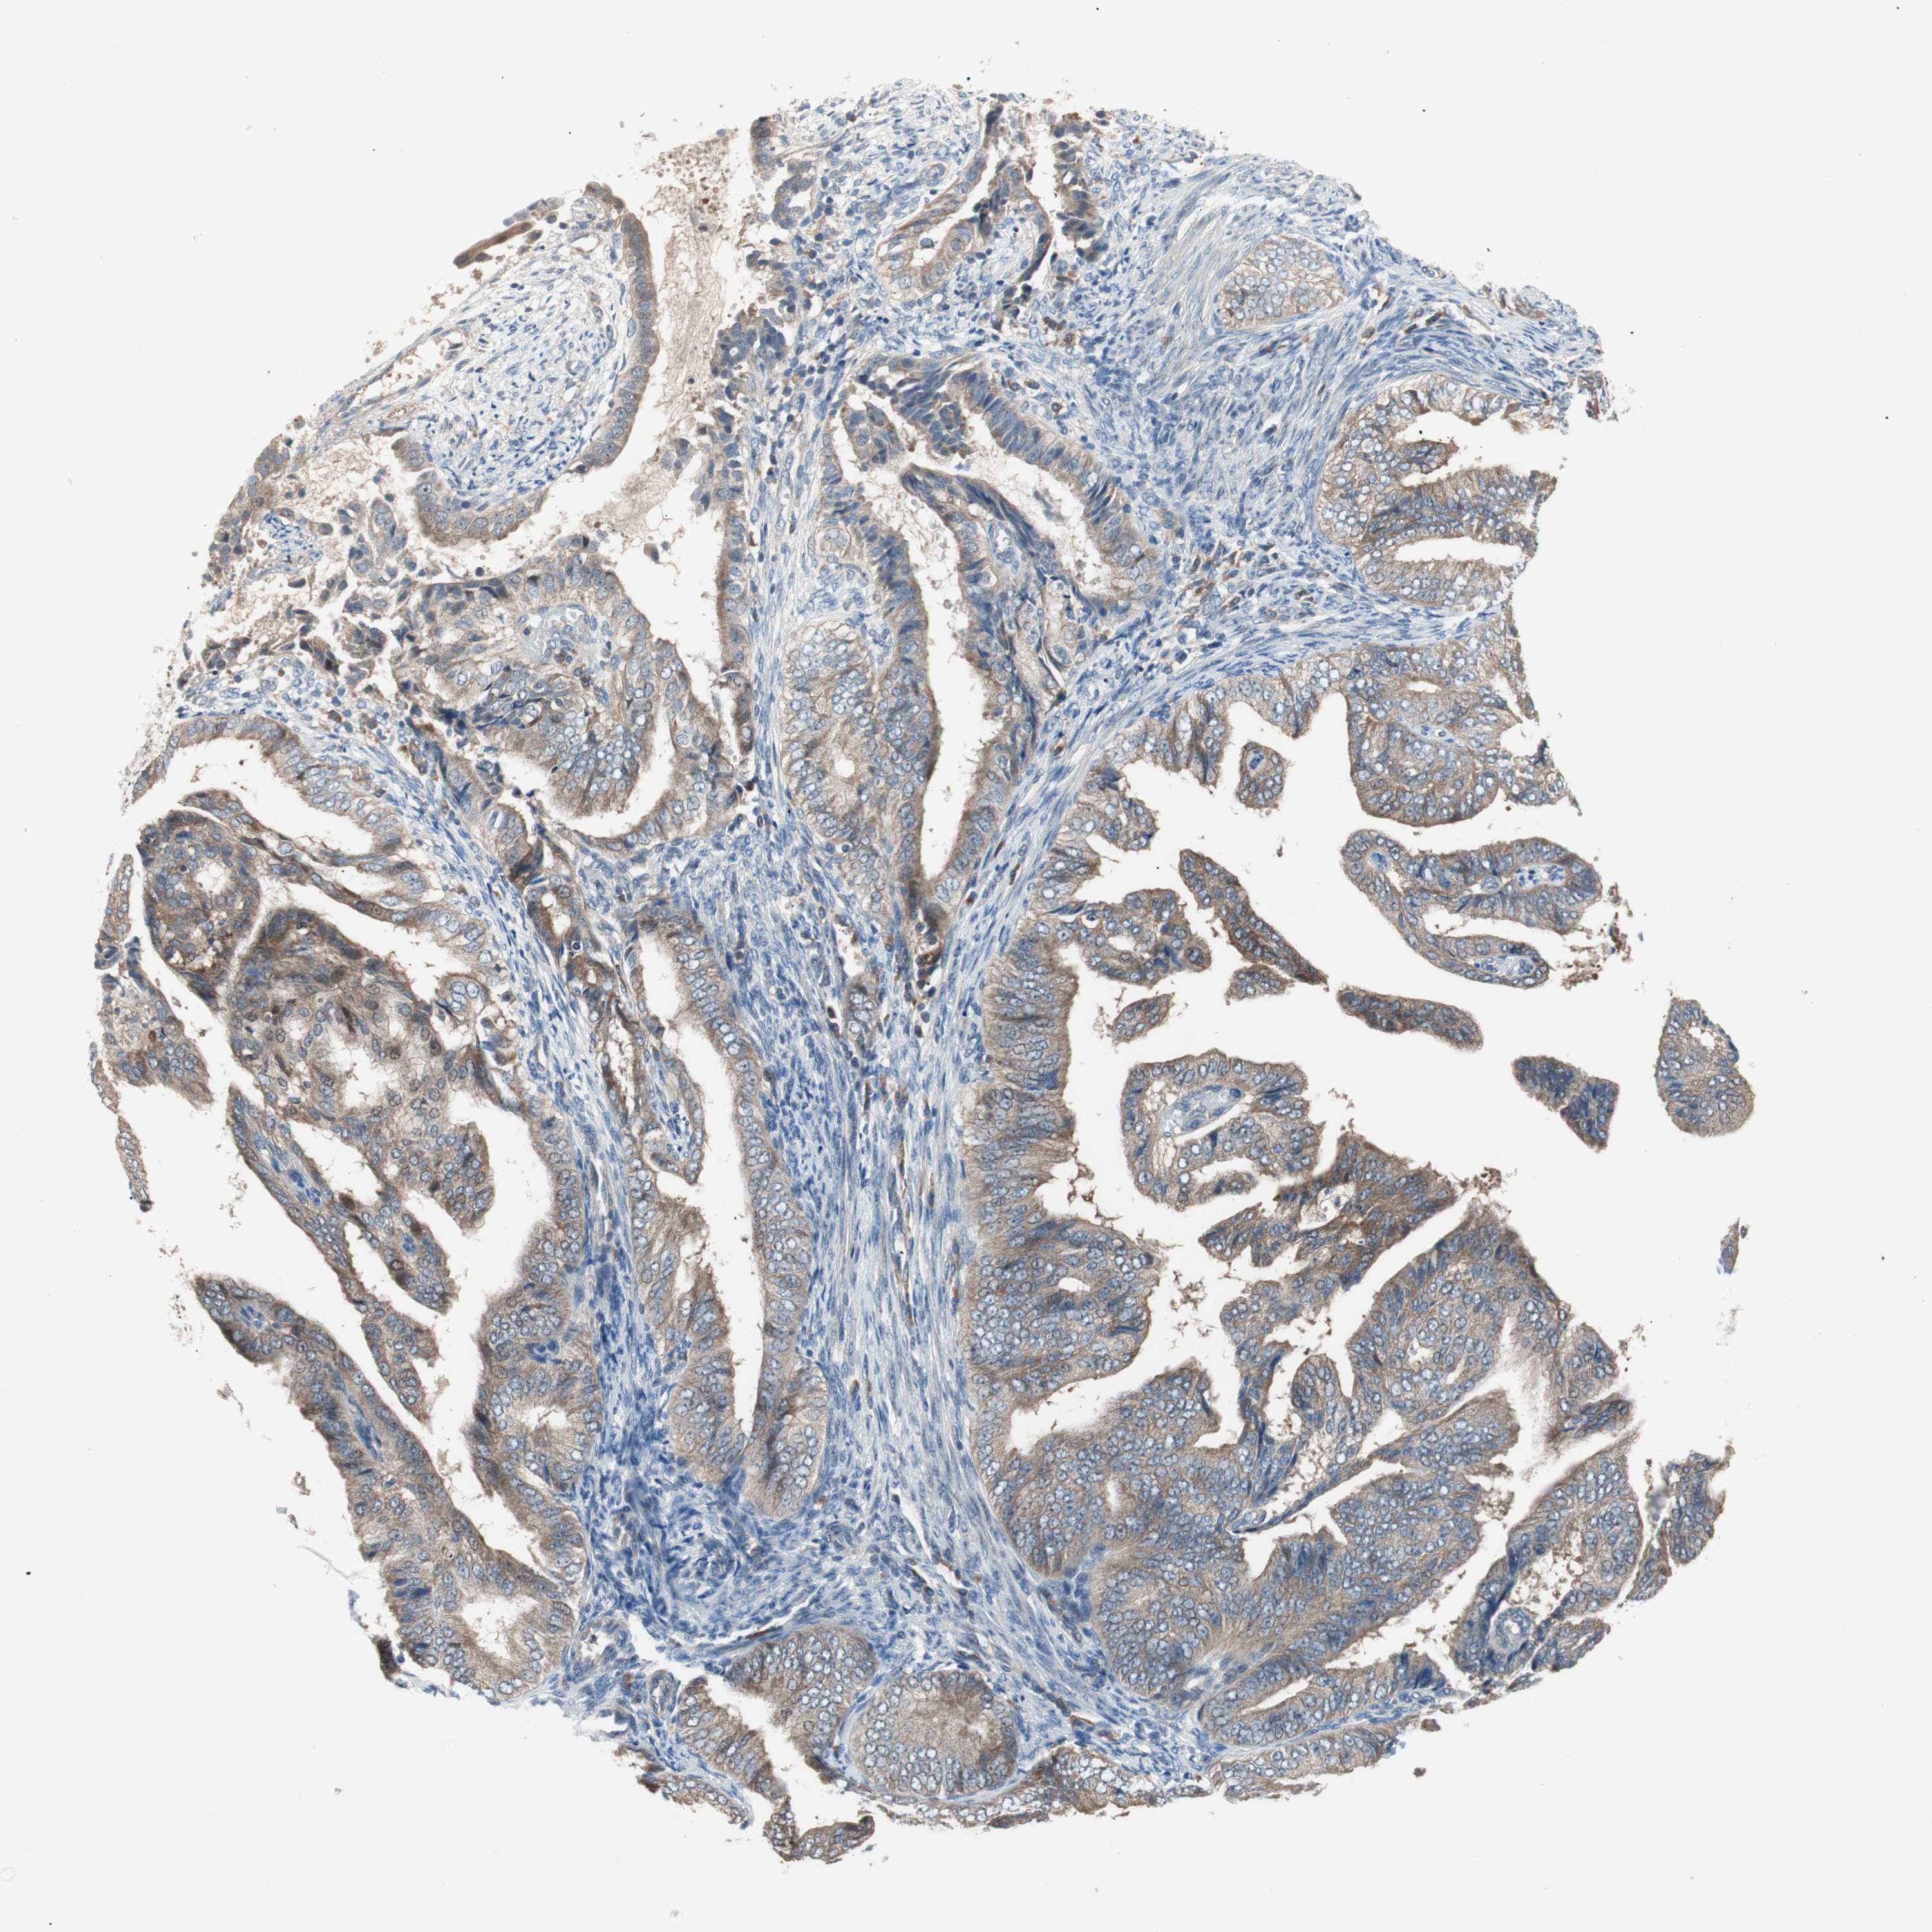

ENDOMETRIAL CANCER - Protein expressioni

A mouse-over function shows sample information and annotation data. Click on an image to view it in a full screen mode. Samples can be filtered based on level of antibody staining by selecting one or several of the following categories: high, medium, low and not detected. The assay and annotation is described here.

Note that samples used for immunohistochemistry by the Human Protein Atlas do not correspond to samples in the TCGA dataset.

Antibody stainingi

Antibody staining in the annotated cell types in the current human tissue is reported as not detected, low, medium, or high, based on conventional immunohistochemistry profiling in selected tissues. This score is based on the combination of the staining intensity and fraction of stained cells.

Each image is clickable and will lead to virtual microscopy that enables deeper exploration of all samples and also displays staining intensity scores, fraction scores and subcellular localization as well as patient and tissue information for each sample.

Antibody HPA006277

Antibody HPA006507

Antibody CAB017027

Staining

High

Medium

Low

Not detected

Intensity

Strong

Moderate

Weak

Negative

Quantity

>75%

75%-25%

<25%

None

Location

Nuclear

Cytoplasmic/membranous

Cytoplasmic/membranous,nuclear

Adenocarcinoma, NOS